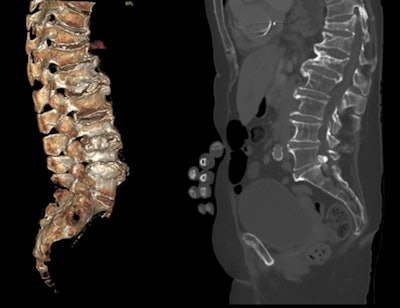

Radiologists and reporting radiographers are well-placed to diagnose VFFs on any modality that can provide images of the spine, including x-ray. All images courtesy of Dr. Anagha Parkar, Bergen, Norway.These are the 12 key points in the RCR guidance:

- Implement a policy of automatic sagittal spinal reformatting and display and storage on PACS for cross-sectional imaging studies that include the spine.

With body CT scanning, performing sagittal bone reformats of the spine does not require additional scan times or radiation dose, nor does it require significant additional storage space. To increase VFF detection on body CT, sagittal reconstruction of the spine using bone windows should be sent routinely to PACS for storage and display."Emerging AI technology and algorithms have scope to support the identification of VFFs through routine scrutiny of cross-sectional imaging via PACS and the creation of 'alert lists' of those patients with suspected VFFs. Radiological interpretation may still be required to verify absence or presence of AI-identified VFFs since this technology is currently limited in differentiating between VFFs and non-fracture deformities such as Scheuermann's disease or Schmorl's nodes," the authors stated.